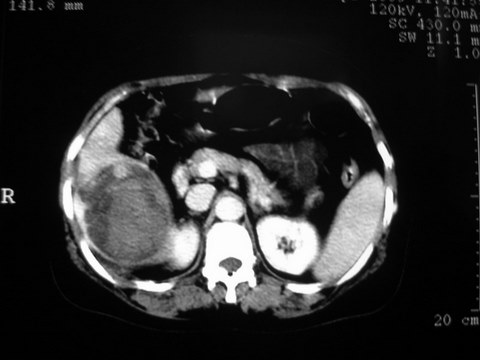

患者 女 51岁 两天前感觉上腹疼,无明显诱因,b超示肝右叶囊实性占位,边缘清楚,其内回声不均匀,ct增强如图,大家看看是什么 ,病人一年前及两月前b超检查只是提示胆囊炎

外院术后,证实肝癌合并出血

出病理 中分化肝细胞癌合并出血